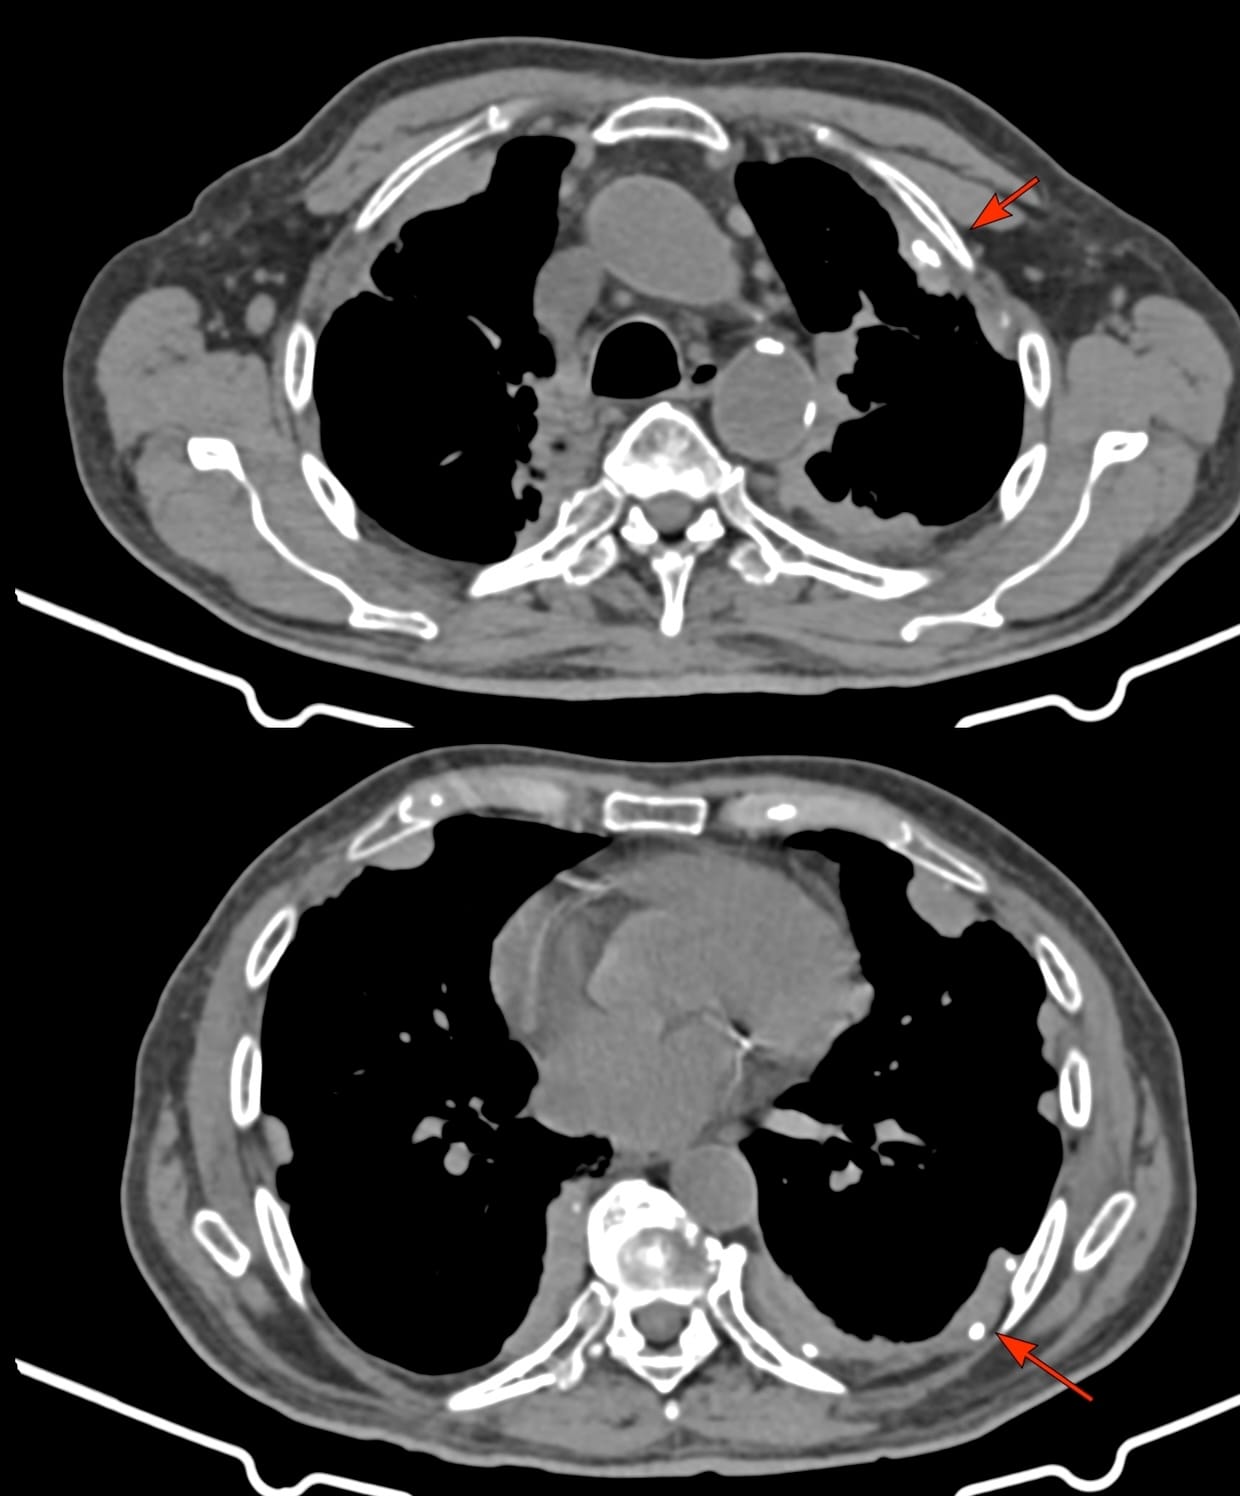

The CT scan showed extensive pleural plaques (arrows), some calcified, some not.

This is characteristic asbestos exposure related pleural disease.

On extensive questioning, the son said that he worked for almost 30 years, from age 25 in the ship building and ship breaking industry which confirmed the asbestos exposure.